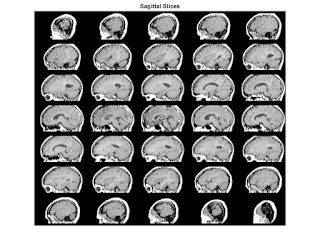

T3 = maketform('affine',[-2.5 0 0; 0 1 0; 0 0 0.5; 68.5 0 -14]); S = tformarray(D,T3,R3,[4 1 2],[1 2 4],[66 128 35],[],0); S2 = padarray(S,[6 0 0 0],0,'both'); figure, montage(S2,map) title('Sagittal Slices'); M1 = D(:,64,:,:); size(M1) M2 = reshape(M1,[128 27]); size(M2) figure, imshow(M2,map); title('Sagittal - Raw Data');

T3 = maketform('affine',[-2.5 0 0; 0 1 0; 0 0 0.5; 68.5 0 -14]);

S = tformarray(D,T3,R3,[4 1 2],[1 2 4],[66 128 35],[],0);

S2 = padarray(S,[6 0 0 0],0,'both');

figure, montage(S2,map)

title('Sagittal Slices');